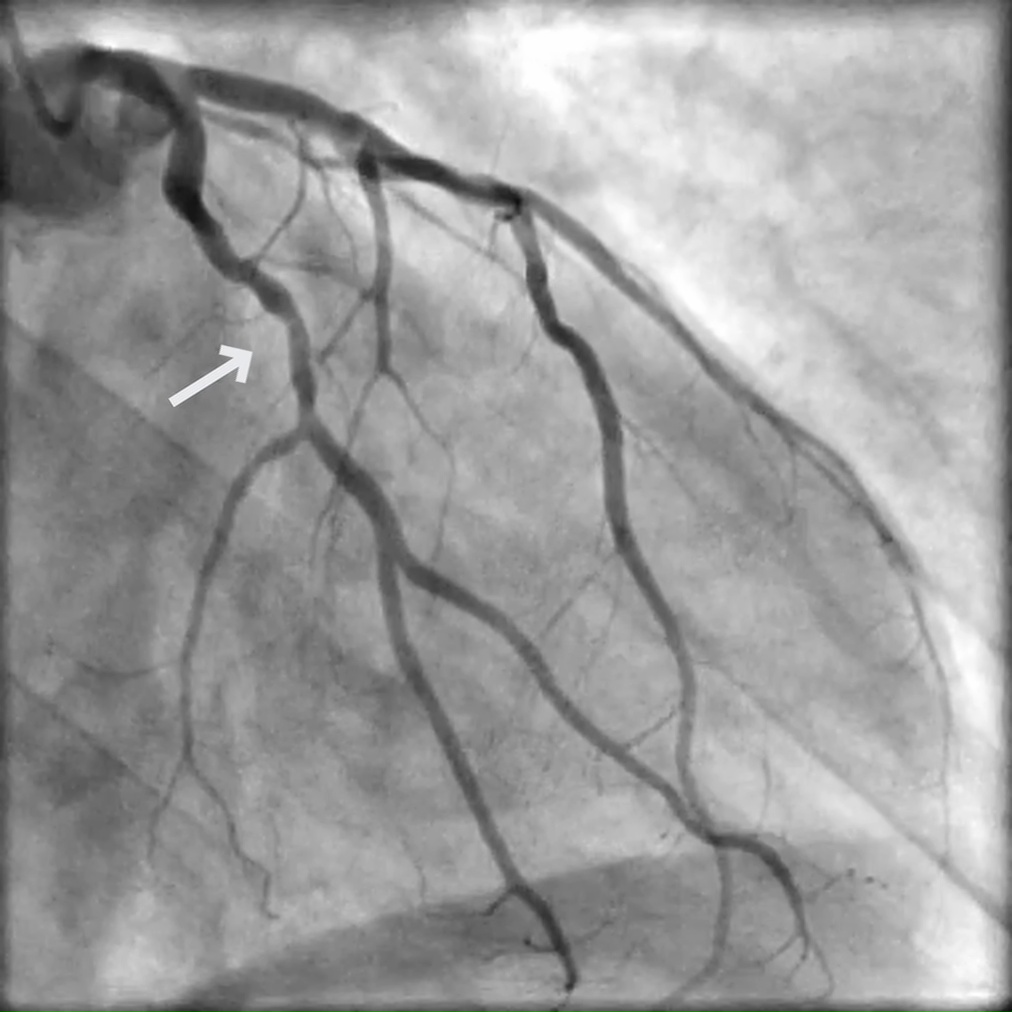

A 65-year-old female with multiple cardiac risk factors presented with exertional angina and shortness of breath (SOB), and had a positive stress test (ETT+).